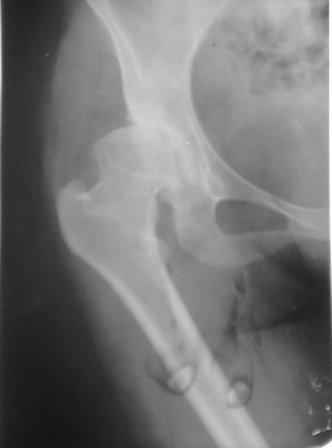

При определении показаний к м/в остеотомии учитываем не только функциональное состояние, но анатомическую форму сустава. Например, при той форме, что на картинке в вашем письме (мелкая впадина,уже не сферичная головка)НИИТО вполне обосновано предлагает ТЭП. Варизирующая остеотомия в "чистом виде" усилит конфликт в опорной зоне сустава. Если очень "настоятельно просит" - экстензия с наружной ротацией по R.Bombelli. То есть на открытом суставе бедро согнуть и ротировать внутрь до покрытия головки впадиной. Сформировать канал через шейку в головку с тем расчетом, что после м/в распила бедро нужно вывести в функциональное положение. Фиксировать 90 град. медиализирующей ортопедической пластиной с клинком. Но выздоровления не обещать, покрытие головки малое, длительного эффекта не будет. Нужна периацетабулярная остеотомия или пластика крыши, но это другая сложность и другая травматичность. Необходимость ТЭП оттянете лет на 10 в лучшем случае. Надо учитывать, что в этом случае ТЭП операция не первая, это увеличивает инфекц. риски и снижает функциональный результат для сустава. Я бы рекомендовал трость с противоположной стороны, ЛФК на приведение, чтобы подрос оссификат крыши и сформировались оссификаты головки. При нормотрофическом типе поражения можно будет провести вальгизирующую остеотомию, эффект которой более длительный или больная за это время найдет возможности приобретения ЭП.

Данный сустав в начальной стадии разрушения, но все-таки я бы сделал обзорный таз и отдельные снимки сустава в 30 градусной абдукции и аддукции. Также снимки с внутренней и наружной ротацией для оценки состояния головки бедра.

Представляю Р-снимки: обзорная, с отведением и с приведением.

Глубокоуважаемый Абдурашид. Здесь нет снимка с отведением. Если Вы сами сходили в рентгенкабинет и лично отвели пораженную конечность максимально возможно, а также дали максимально возможную внутреннюю ротацию-это одно!!!! Значит у пациентки тяжелейшая приводящая контрактура тазобедренного сустава!! И необходимо разобраться-миогенная или артрогенная? Если же Вы просто назначили указанный снимок и доверили произвести укладку рентгентехнику-это другое!!! Одному богу известно, что она делала, ведь на р-снимке отведения нет!

Все предыдущие корреспонденты предлагают вам достаточно простую вещь-смоделировать предлагаемую Вами операцию (т.е. дать отведение и внутреннюю ротацию) и посмотреть, как изменятся соотношения в суставе. Не обижайтесь, но судя по представлению клинического случая угловые величины, характеризующие пространственные соотношения в тазобедренном суставе, ваши рентгенологи не считают.

Уважаемый Игорь Владимирович. диссертации М М Камоска, и В Е Баскова я нашел, но почему-то не могу открывать, и еще в данном случае имеется дисплазия т/б за счет недоразвития крыши в/впадины да и всей подвздошной кости, маргинального вывиха или латеропозиции головки вследствие лечебных ощибок нет, головка стоит на месте. Р-граммы сделал сам, но почему-то у больной отведение и внутренная ротация стали очень болезненной, и сухожилия приводящих мышц сильно натягивается.(контрактура артро-миогенная).

Глубокоуважаемый Игорь Владимирович! Признаюсь допустил ошибку, из-за напряженности работы и нехватки времени, когда повторно внимательно посмотрел все понял и не успел исправить ошибку до Вашего поста, конечно скошенность крыши в пределах 40гр,часть головки кнаружи линии Омбредана-Перкинса , облитерация дна вертлужной впадины и т.д.-это ДМВБ.